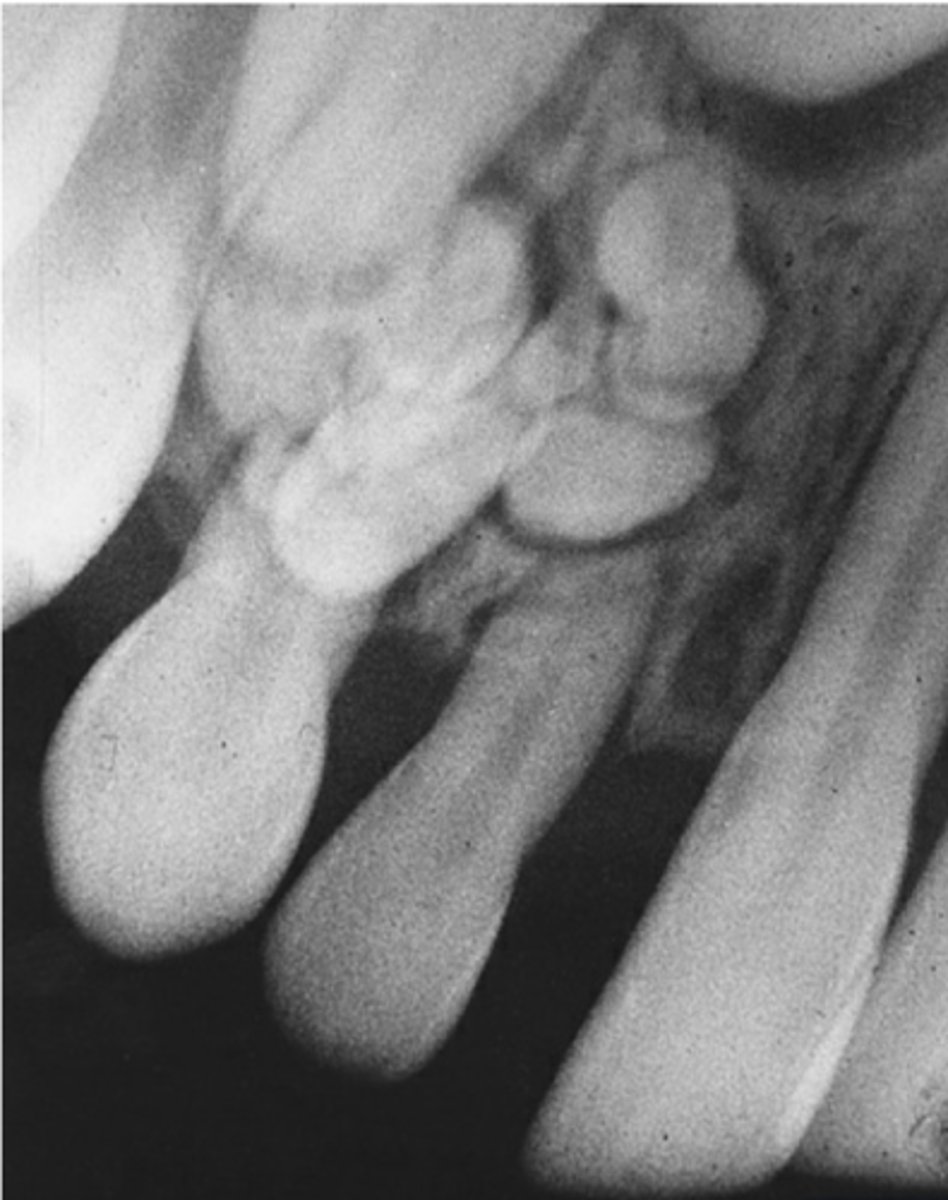

What are the radiographic features of ameloblastomas?

⢠unilocular radiolucency (early lesions)

⢠multilocular radiolucency (honeycomb/soap bubble) (large lesions)

⢠cortical thinning/bone expansion

⢠resorption of adjacent tooth roots + tooth displacement